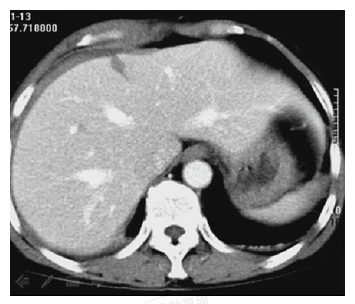

試題3:患者女性,50歲,間斷上腹隱痛半年,診斷為(2分)

A.肝癌

B.肝硬化

C.膽囊結(jié)石

D.腎結(jié)石

E.急性膽囊炎

【答案】C